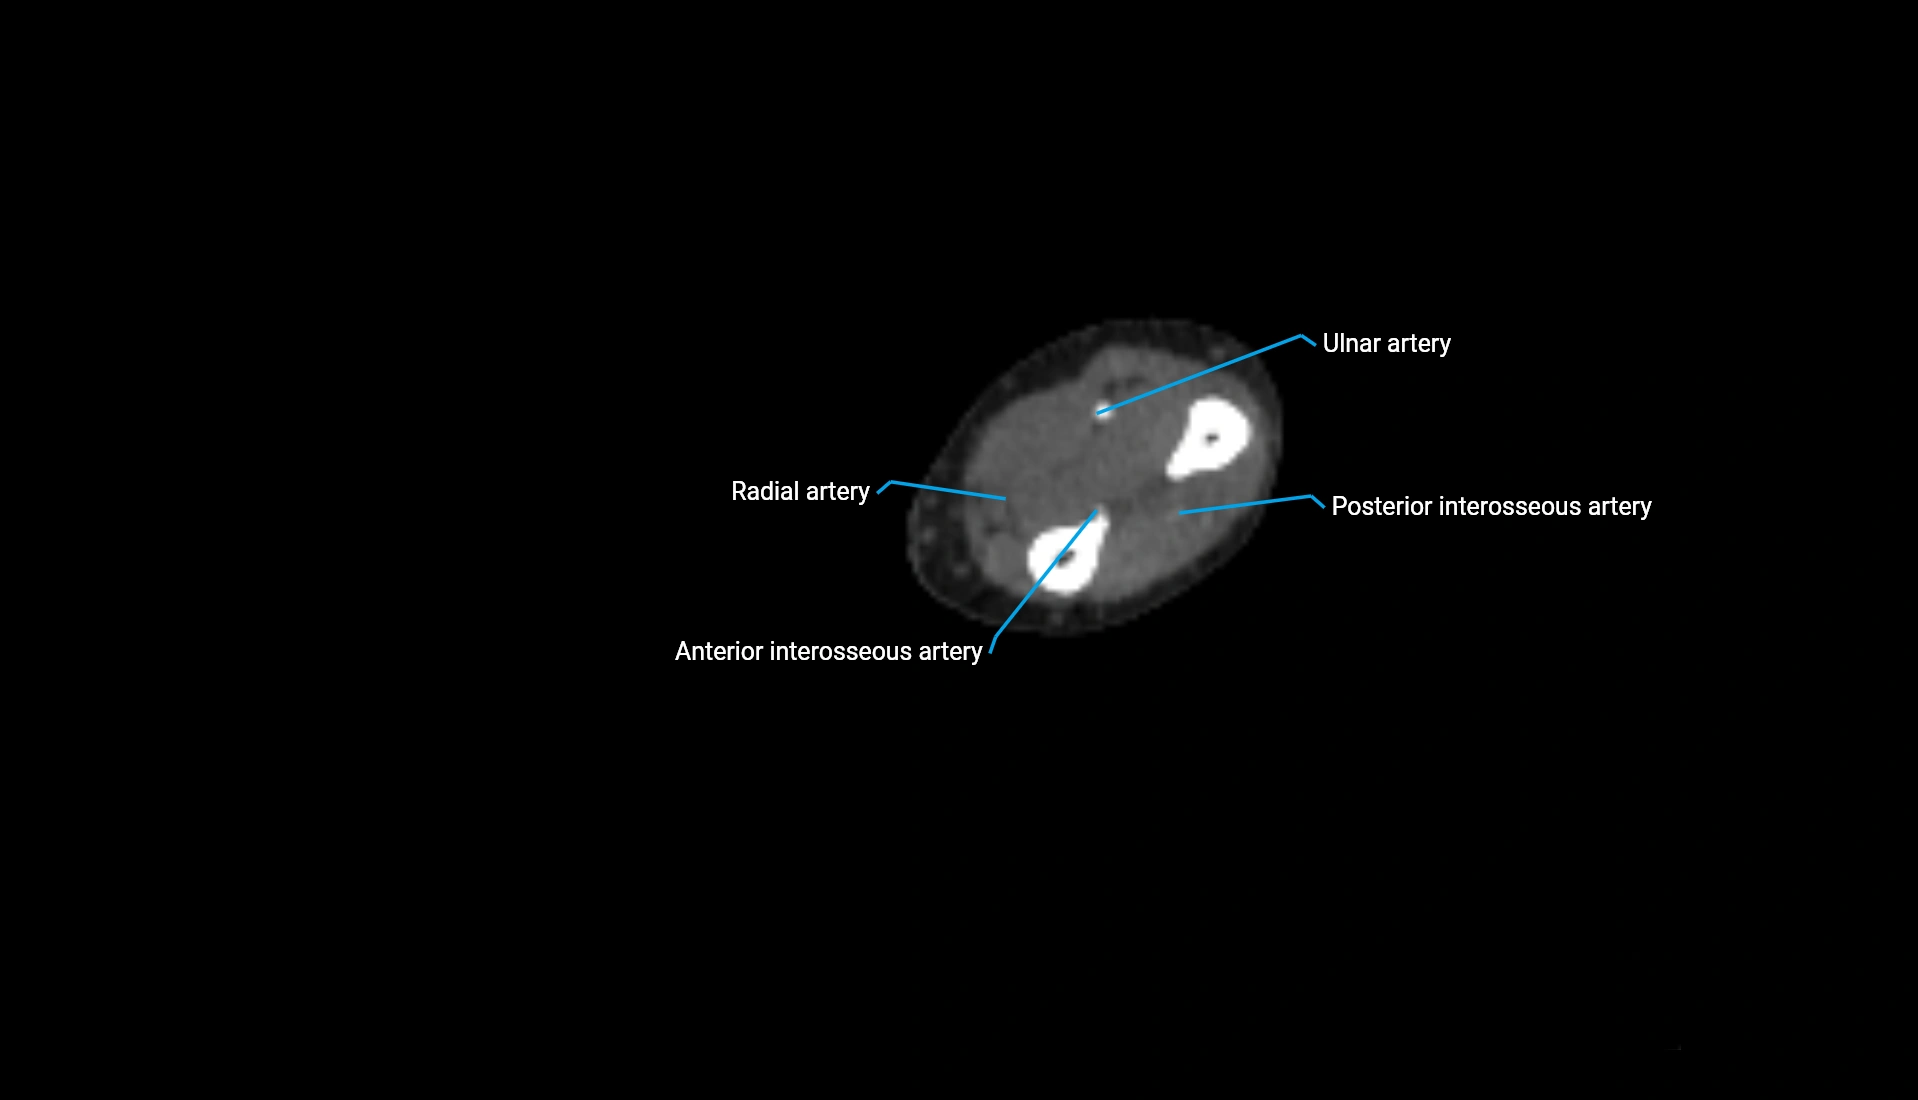

CT Appearance

Non-Contrast CT:

• Cortex: High-density, sharply defined

• Subchondral bone: Dense cancellous matrix

• Articular surface: Smooth concave contour articulating with the capitellum

• Excellent for evaluating bone integrity, alignment, and subtle fractures